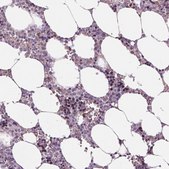

由Atlas Antibodies提供技术支持的所有Prestige Antibodies抗体均由人类蛋白质图集(HPA)项目开发和验证,因此受到业内最广泛的表征支持。

人类蛋白质图集项目可以分为三大部分: 人体组织图谱、癌症图谱和人类细胞图谱。在组织和癌症图谱项目支持下产生的抗体已通过对数百种正常和疾病组织的免疫组织化学分析得到了验证,并且通过近期人类细胞图谱项目的努力,许多抗体已经过免疫荧光分析的表征,从而绘制人类蛋白质组图谱,不仅是在组织水平上,现在已经达到亚细胞水平。在人类蛋白质图集项目网站上单击图像库链接,可以查看这些图像和庞大的数据集。我们还提供Prestige Antibodies® 抗体的实验方案和其他有用信息。

• 44种正常人体组织和20种最常见癌症组织的IHC组织阵列。